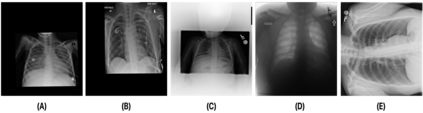

Medical image analysis continues to hold interesting challenges given the subtle characteristics of certain diseases and the significant overlap in appearance between diseases. In this work, we explore the concept of self-attention for tackling such subtleties in and between diseases. To this end, we introduce MEDUSA, a multi-scale encoder-decoder self-attention mechanism tailored for medical image analysis. While self-attention deep convolutional neural network architectures in existing literature center around the notion of multiple isolated lightweight attention mechanisms with limited individual capacities being incorporated at different points in the network architecture, MEDUSA takes a significant departure from this notion by possessing a single, unified self-attention mechanism with significantly higher capacity with multiple attention heads feeding into different scales in the network architecture. To the best of the authors' knowledge, this is the first "single body, multi-scale heads" realization of self-attention and enables explicit global context amongst selective attention at different levels of representational abstractions while still enabling differing local attention context at individual levels of abstractions. With MEDUSA, we obtain state-of-the-art performance on multiple challenging medical image analysis benchmarks including COVIDx, RSNA RICORD, and RSNA Pneumonia Challenge when compared to previous work. Our MEDUSA model is publicly available.